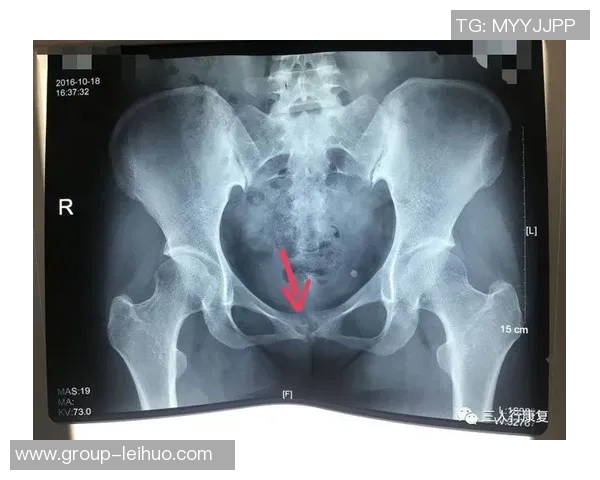

尼科·威廉姆斯是一名备受瞩目的年轻球员,他在比赛中表现出色,为球队贡献了许多关键进球。然而,在一次重要比赛中,他不幸遭遇了耻骨炎。这种疾病给他的训练和比赛造成了严重影响,让他不得不面对漫长而艰难的恢复过程。

初期,尼科并没有意识到自己的伤势有多严重。他依旧坚持参加训练,但随着时间推移,他逐渐感受到身体的不适。经过专业医生的检查后,他被确诊为耻骨炎,这让他深感沮丧,因为这意味着他需要停下脚步,进行长时间的康复治疗。

从确诊开始,尼科·威廉姆斯便积极配合医生制定了一套详细而科学的康复计划。这个计划包括物理治疗、药物调理以及特定动作训练等多个环节,以帮助减轻疼痛和加快康复速度。同时,他也开始注重饮食,通过合理营养来增强身体抵抗力。